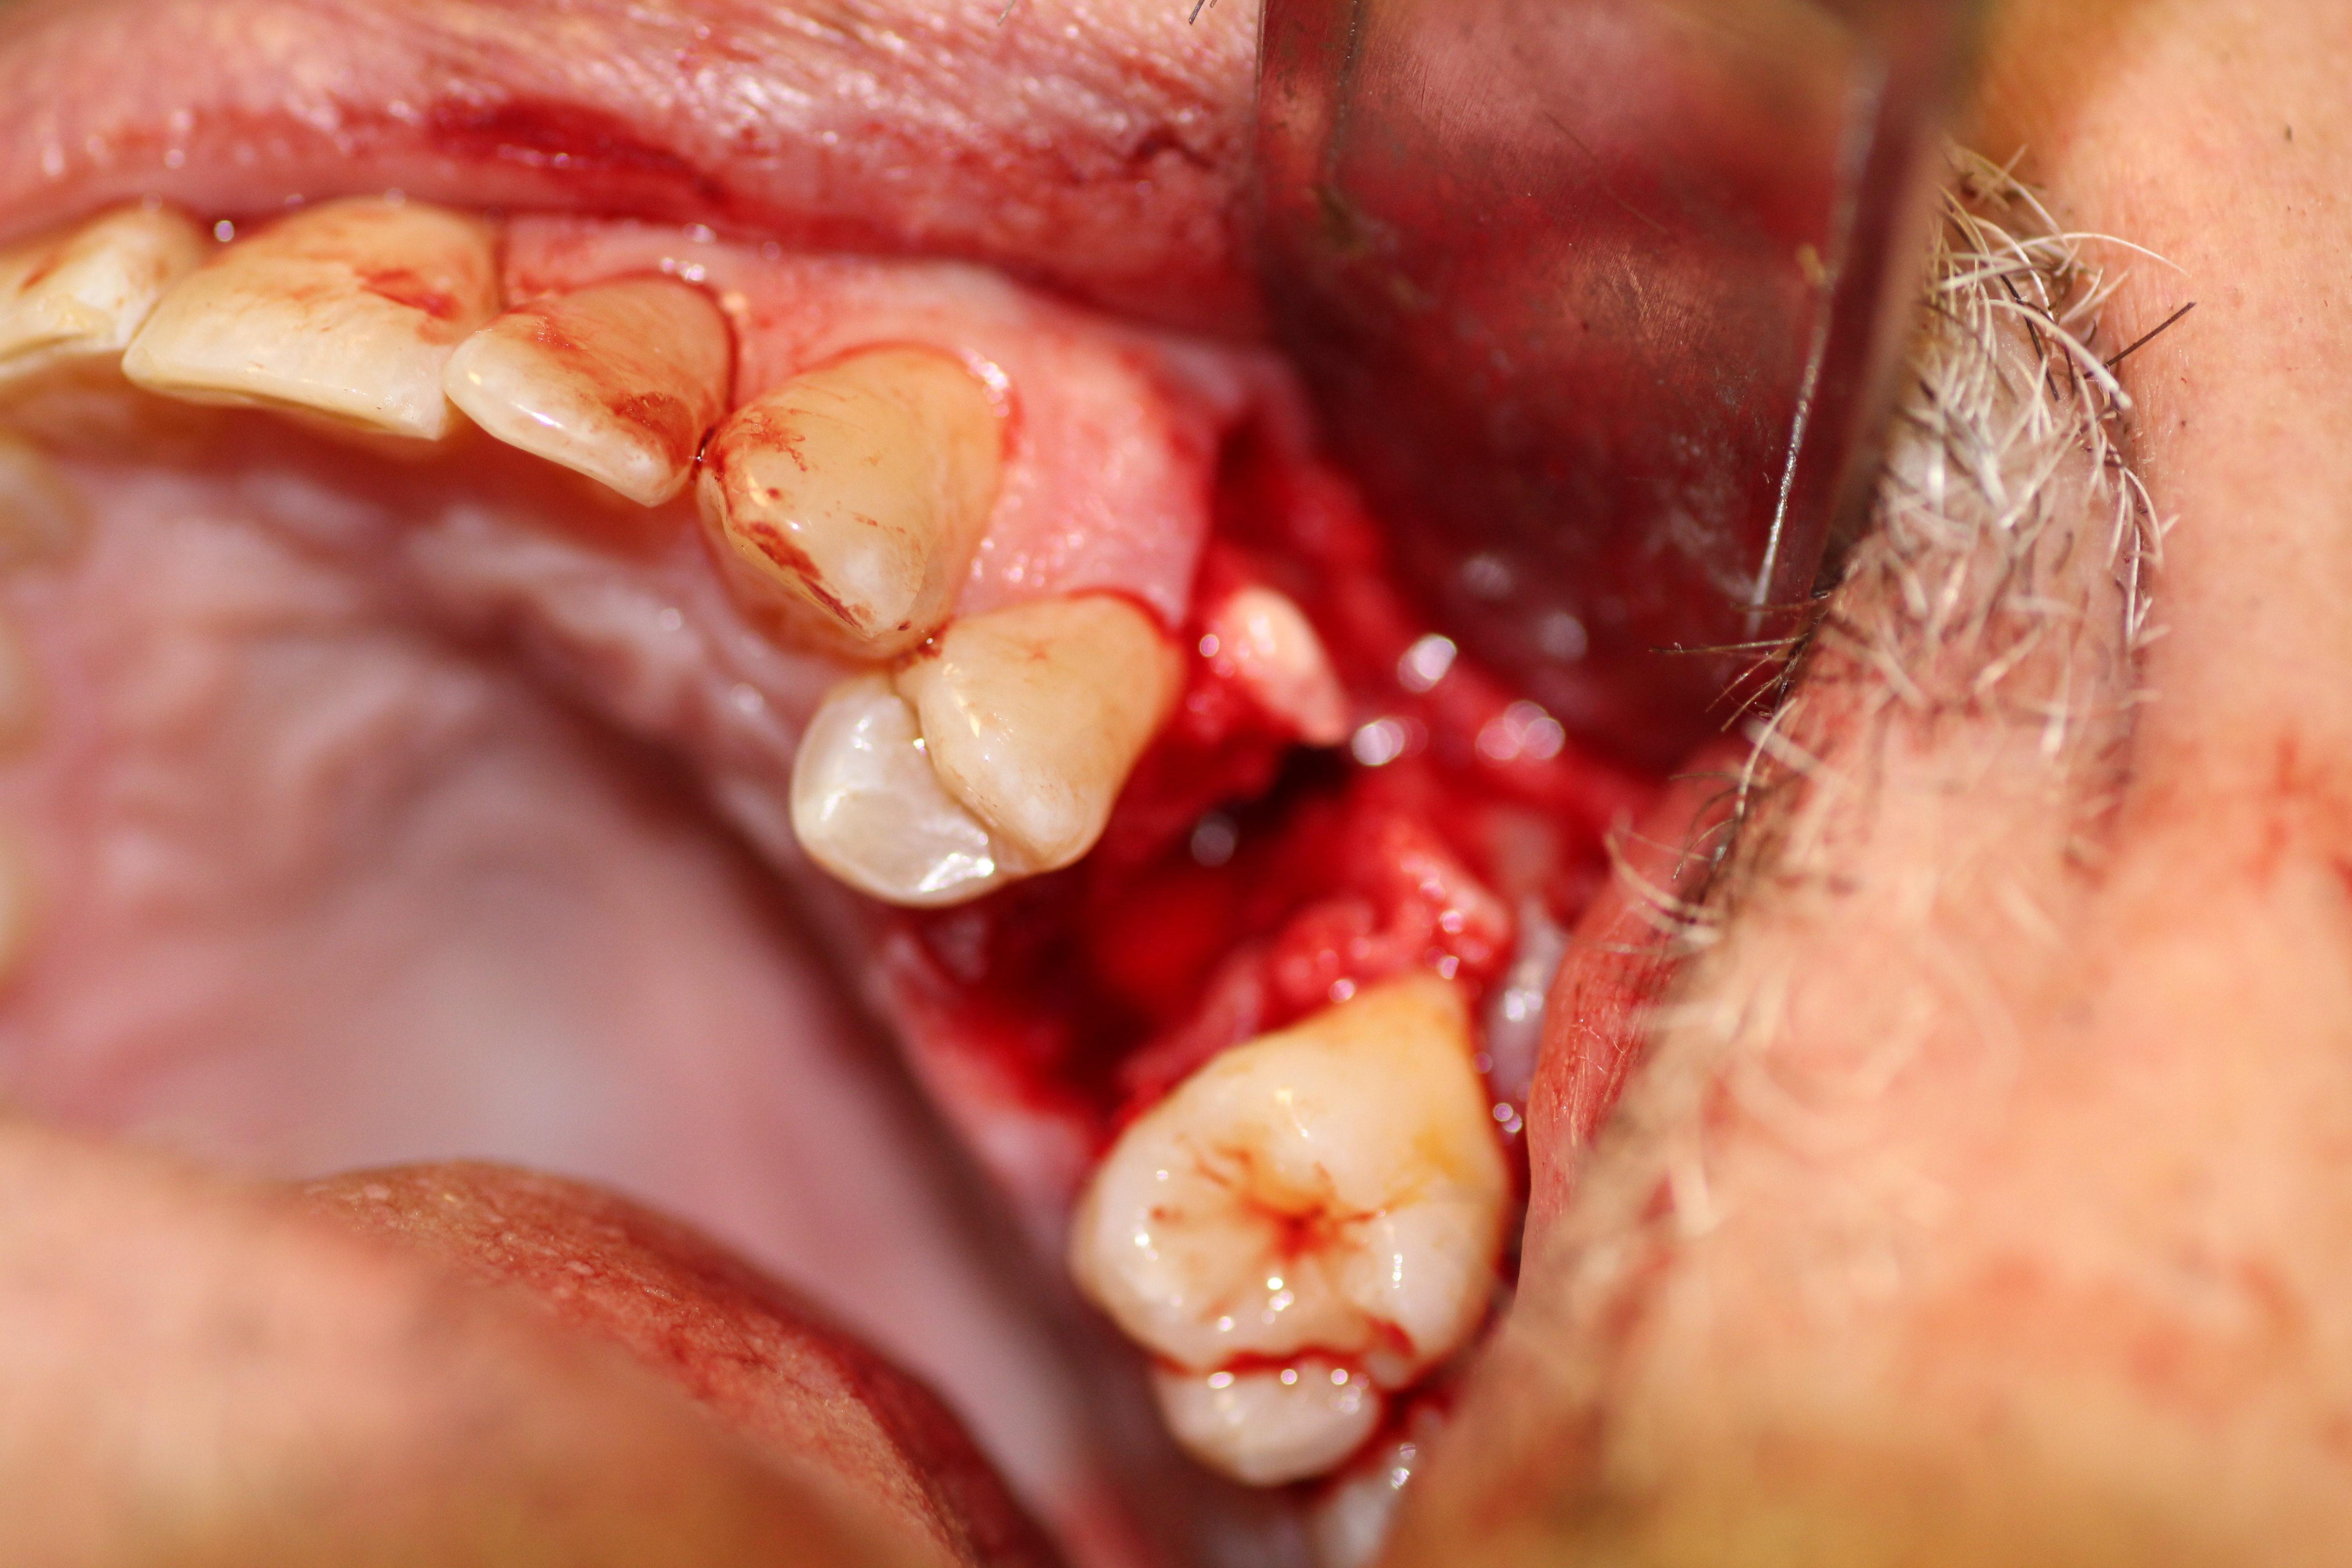

Case #2

Extraction and immediate implant placement with guided bone regeneration.

- Tooth extraction complete.

- A large bony defect on the buccal wall.